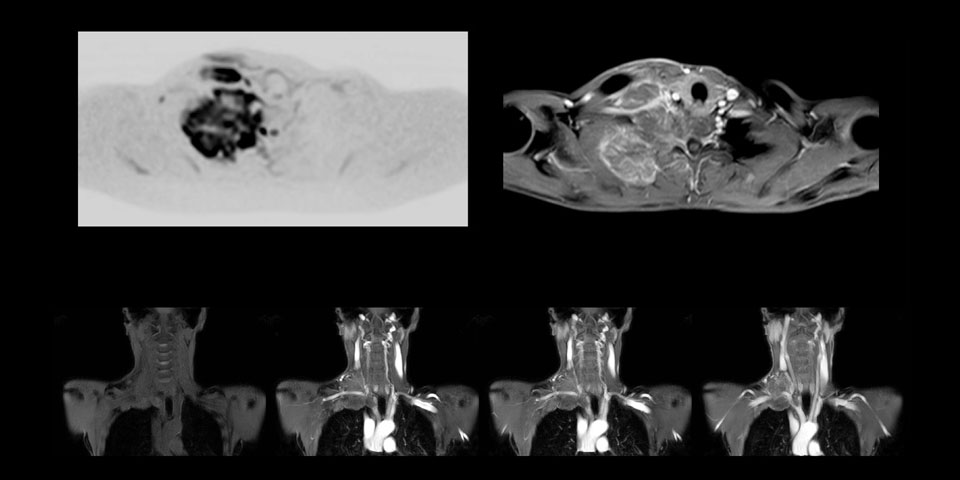

Although the area between the neck and the top of the lung is one of the most difficult areas for MRI, Prodiva 1.5T images show good quality in this 56-year-old male with Pancoast tumor on the right. mDIXON TFE images shows excellent fat suppression in the neck area and the DWI shows almost no distortion.